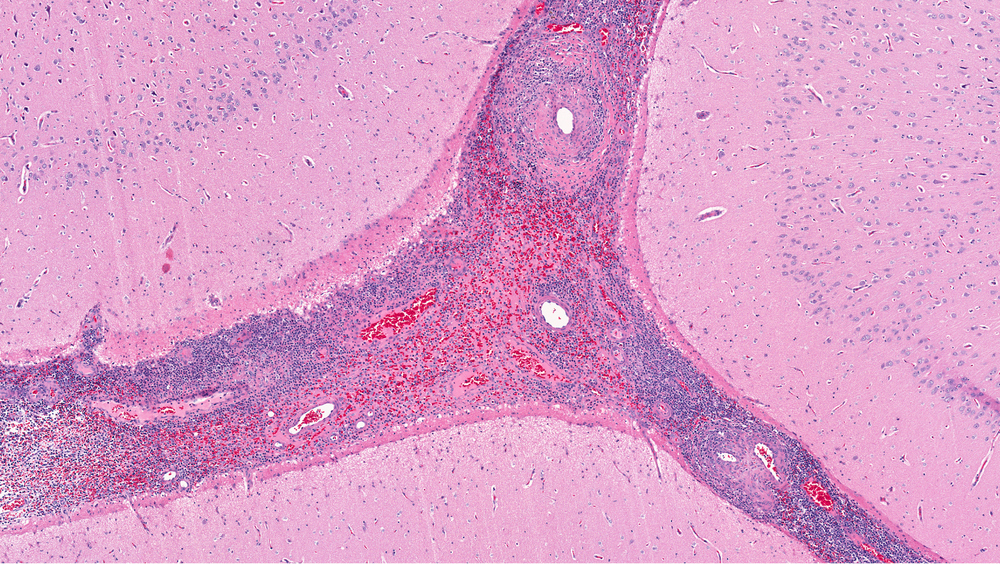

Васкулит поражает крупные, средние и мелкие сосуды, вызывая неприятные симптомы. Заболевание может быть смертельно опасным, если вовремя не начать лечение. На какие симптомы нужно обратить внимание и как лечить васкулит? Что такое васкулит Васкулит – это воспалительный процесс, который запускается в кровеносных сосудах организма. Патология может затронуть мелкие (капилляры), средние и даже крупные сосуды. В зависимости от пораженных сосудов, васкулит приводит к ухудшению кровообращения, вызывает тромбозы, одышку, инфаркт и другие болезни. Васкулит бывает двух типов: Первичный – заболевание развивается самостоятельно и не вызвано другими проблемами со здоровьем. Вторичный – в этом случае патология возникает как реакция на другие болезни в организме. Причины васкулита В большинстве случаев точная причина возникновения патологии неизвестна. Более того, воспаление сосудов может развиться даже у здоровых людей. Тем не менее, в данном случае важную роль играет иммунная система, которая созда

Васкулит – это воспалительный процесс, который запускается в кровеносных сосудах организма. Патология может затронуть мелкие (капилляры), средние и даже крупные сосуды. В зависимости от пораженных сосудов, васкулит приводит к ухудшению кровообращения, вызывает тромбозы, одышку, инфаркт и другие болезни.